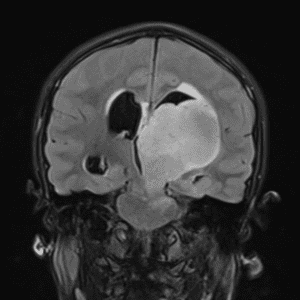

Case #42

Giant cerebral aneurysm